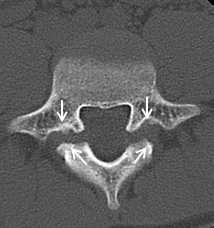

【術前】

CT検査で関節突起部に腰椎分離症を認めています。若年者の腰痛の原因となります。

【術後】

CT検査で関節突起部の骨移植を伴う分離部修復術を施行し骨癒合が得られています。